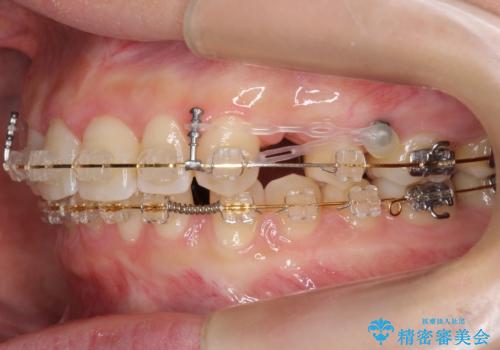

前歯のすきま 右上の小臼歯の垂直的骨吸収を抜歯で解決

- 審美装置

- 前歯のすきまを気にして来院。

奥歯が1歯対1歯で、過蓋咬合を呈していました。

レントゲンで、右上4番の近心の垂直的骨欠損があり、抜歯を行うこととしました。

それがなければ上顎歯列の遠心移動をすることで、非抜歯でマウスピース矯正でも可能であったと思います。

垂直的骨欠損は咬み合わせから起こったものと推察されました。

short faceであり、結果上顎の臼歯を近心に大きくロスさせることになったたため、非常に長く治療期間はかかりました。